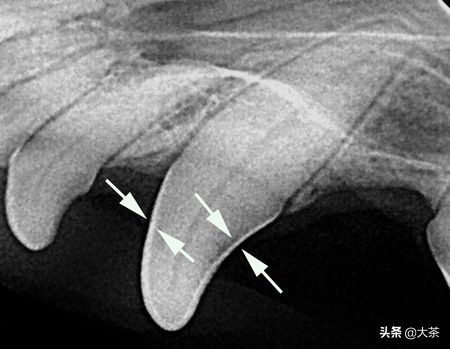

从X光片上可以清楚地看到牙釉质,由于密度高,它的颜色最白

牙釉质里面包裹的是牙本质,牙本质的硬度比牙釉质低一些,里面布满了细小的管道,与最里层的牙髓相通。